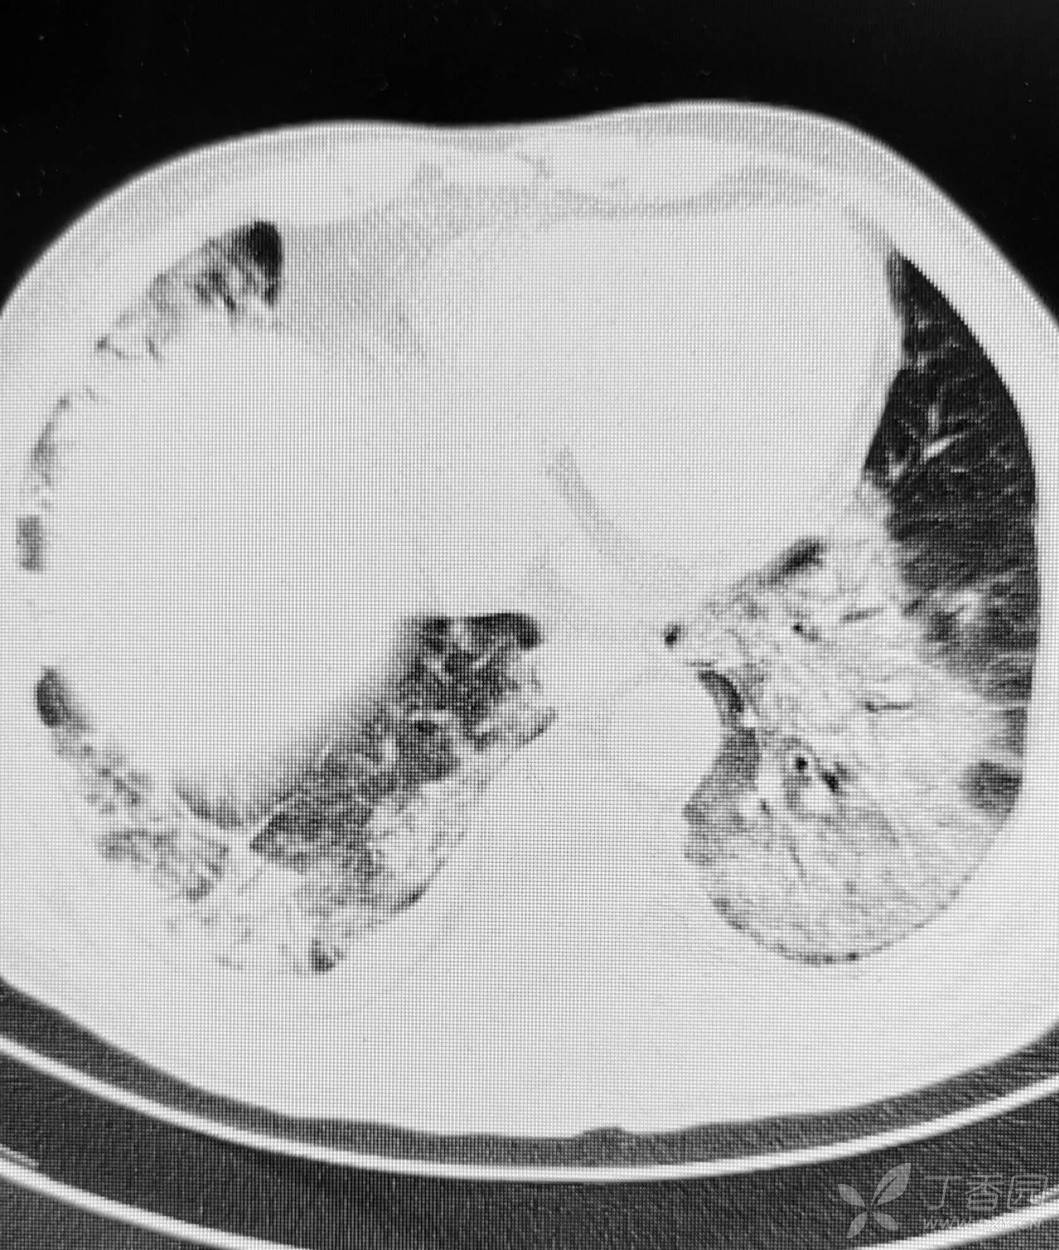

直肠癌术后两个月,接受放化疗一个月。白细胞危急值。

停化疗放疗,升白药物。白细胞增高了。

血小板仍低,血红蛋白开始降低。

胸部影像如图。

目前有血培养阳性,病原菌难以命中。痰培养阳性。